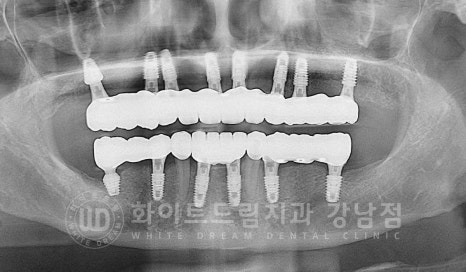

▲ 치주염 전체임플란트 치료 사례

오늘은 이 치주염으로 전체 임플란트 치료를 진행하신 40대 여성분의 치료 사례를

알아보려 하는데요.

상/하악 임플란트 식립을 모두 마친 후

이식한 뼛가루가 새로운 뼈로 형성되고, 임플란트가 새로운 뼈와 단단하게 굳는

회복 기간을 거치게 됩니다.

임플란트 회복 기간은 환자분의 치료 전 상태에 따라서 달라지며

빠르면 3개월 길면 6개월까지 기간을 잡고 임플란트의 회복 양상을 지켜보게 됩니다.

환자분은 4개월의 회복 기간을 거친 후 잇몸뼈 안에 매복되어 있던

16,36,46번 임플란트를 겉으로 노출시키는 2차 수술을 진행했고

이후 바로 임플란트 인상채득 & 최종 보철 제작에 들어갔습니다.

환자분 구내에 세팅된 최종 크라운입니다.

초기 계획에 따라 낮아진 수직 고경도 어금니 임플란트 보철을 세팅을 통해

정상 교합 높이를 회복한 것이 확인됩니다.^^